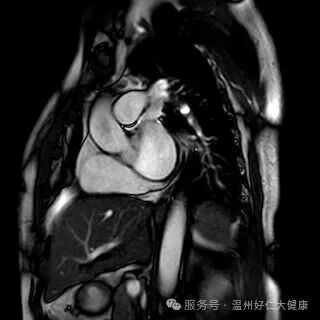

别让猝死 “突袭”!冠脉磁共振精准筛查,守护心脏安全

针对心脑血管早筛的核心需求,我院全力推进冠脉磁共振检查技术普及,凭借无创、无辐射、不打造影剂的硬核优势,攻克传统筛查的痛点,成为不同人群冠脉血管筛查的优选方案,让早期血管病变无所遁形:无创安全,适配全人群:全程无需插管、不注射造影剂,从根源规避造影剂过敏、肾脏代谢负担等问题,肾功能不全、备孕、造影剂过敏等特殊人群也能安心检查,真正实现 “零负担筛查”; 零辐射高精准,捕捉隐匿病变,无任何电离辐射,即使多次复查也不会对身体造成损伤;成像精度可清晰识别冠脉血管软斑、硬斑等斑块性质,精准判断血管狭窄程度,哪怕是早期隐匿的微小病变,也能精准检出; 一站式筛查,兼顾血管与心脏:不仅能排查冠脉血管病变,还能同步评估心肌灌注、心脏收缩舒张功能,清晰呈现心肌细微结构,一站式完成 “血管 + 心脏” 全面检查,为冠心病早期筛查、高危人群动态监测提供精准的诊断依据。